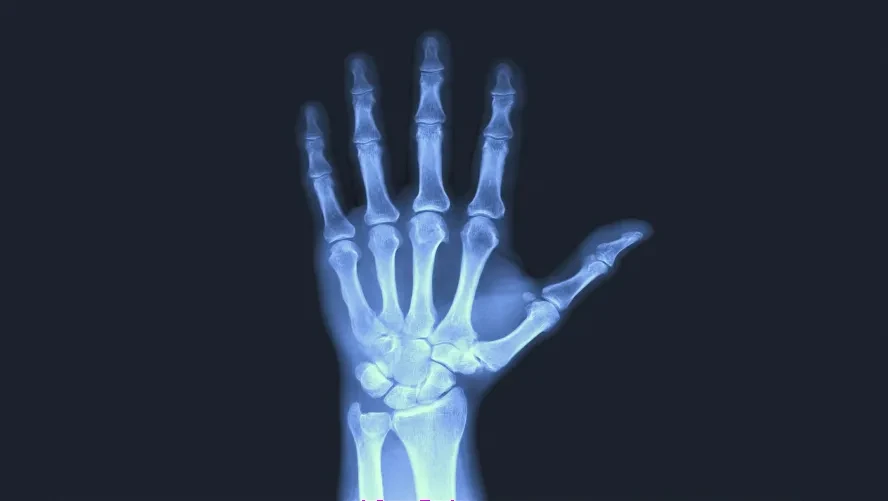

Tendonlar kasların ve kemiklerin birbirine bağlanmasını sağlayan lifli yapılardır. Tetik parmak hastalığı da bu tendonlarda meydana gelen iltihaplar sonucunda görülmektedir. İltihaplanan bu tendonlar zamanla parmakların hareket halindeyken kilitli kalmasına neden olur ve hareket kısıtlılığına neden olur.

Normal insan anatomisinde tendon yapıları eklem kapsülleri üzerinden geçerek kaslar ve kemikler arasında bağlantı sağlar ve iskelet sisteminin hareketini sağlar. Bu tendonların çevresinde dış etkiye karşı koruma sağlayan kılıflar bulunmaktadır. Bu kılıflar çeşitli nedenlere bağlı olarak iltihaplanırsa yaralar oluşmaya başlar ve zamanla tendon sıkışmaya başlar. Zamanla sıkışan bu tendonlar hareketi engeller ve tetik parmak denilen bu hastalığı ortaya çıkarır. Tetik parmak hastalarının dikkat etmesi gerekenler nelerdir, belirtileri nedir gibi soruların cevabını yazımızın devamında bulabilirsiniz.